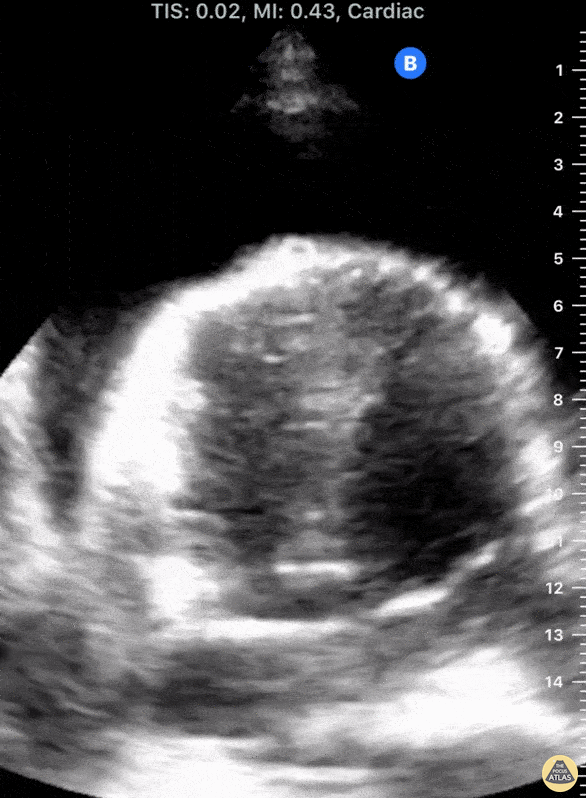

31-yo-male presented s/p syncopal episode and ongoing hypotension. Initial evaluation included POCUS that revealed a circumferential pericardial effusion causing RA and RV diastolic collapse as well as a “swinging heart”. Patient was promptly sent for a pericardial window. Tessa W. Damm, DO Intensivist, Critical Care Medicine & Neurocritical Care Wisconsin, USA @DrDamm